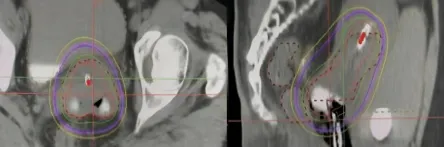

在全球范圍內(nèi),每年大約有20萬名女性死于宮頸癌。在我國,宮頸癌是女性中最普遍的惡性腫瘤之一。目前,宮頸癌的三大主要治療方式包括手術(shù)、放療和化療,其中放療應(yīng)用最廣泛,適合各期宮頸癌患者。三維近距離后裝放射治療技術(shù)能夠在提高腫瘤部位的放射劑量的同時,減少對正常組織的放射損傷,從而降低放射治療的副作用。 近距離后裝放療是“內(nèi)照射”的一種方法,與遠(yuǎn)距離放射治療(外照射)相對。該治療方式將放射源直接置入需治療的區(qū)域,對于宮頸癌患者而言,放射源將被放置于宮頸腫瘤部位進(jìn)行局部照射。若將腫瘤比作敵軍,外照射則如同廣泛布陣,全面覆蓋,但為盡量減少對周圍健康組織的損害,其放射劑量相對較低。而內(nèi)照射則如同對敵軍指揮中心的精準(zhǔn)打擊,劑量較高,集中性強(qiáng)。因此,若缺少內(nèi)照射這一環(huán)節(jié),便缺少了對敵軍指揮中心的精準(zhǔn)打擊,從而增加了腫瘤復(fù)發(fā)的風(fēng)險。 什么是三維近距離后裝放療? 三維近距離后裝放療,是先將施源器放置于接近腫瘤的人體天然腔、管道內(nèi)(如宮腔、陰道等)或?qū)⒖招踞樄苤踩肓鲶w內(nèi);隨后,利用CT或磁共振成像技術(shù)掃描獲取圖像數(shù)據(jù),通過圖像傳輸系統(tǒng)將這些數(shù)據(jù)導(dǎo)入治療計劃系統(tǒng),醫(yī)生根據(jù)患者病情需要確定靶區(qū)范圍,經(jīng)計劃系統(tǒng)計算劑量分布,在獲得理想治療方案后,對腫瘤實(shí)施放射治療。 三維近距離后裝放療的優(yōu)勢 1三維近距離后裝放療每次治療時都有實(shí)時CT/核磁共振圖像引導(dǎo),彌補(bǔ)了二維腔內(nèi)放療不能直視腫瘤的缺陷,能更精確覆蓋腫瘤或瘤床范圍,達(dá)到更好的靶區(qū)覆蓋,實(shí)現(xiàn)靶區(qū)劑量的個體化分布,提高患者生存率,顯著降低復(fù)發(fā)率。 2 三維近距離后裝放療是在CT/核磁共振圖像引導(dǎo)下進(jìn)行的,在圖像上精準(zhǔn)勾畫靶區(qū)和危及器官,后裝計劃系統(tǒng)可以對放射源駐留位置、處方劑量等預(yù)設(shè)參數(shù)進(jìn)行優(yōu)化,提高腫瘤靶區(qū)的照射劑量、降低周圍正常組織的照射劑量。同時應(yīng)用多模態(tài)影像管理系統(tǒng),客觀地在三維的參考面對腫瘤及周邊危及的器官進(jìn)行評估,在保證腫瘤區(qū)域受照劑量的同時,有效保護(hù)膀胱、直腸、小腸等危及器官,減少急性放射性黏膜損傷的發(fā)生。 兩例宮頸癌患者 后裝治療前后影像學(xué)資料 病例1 病例2 門診預(yù)約方式 關(guān)注“滄州市中心醫(yī)院”微信公眾號,或支付寶關(guān)注“滄州市中心醫(yī)院互聯(lián)網(wǎng)醫(yī)院”,點(diǎn)擊“醫(yī)療服務(wù)”—“掛號服務(wù)”—“放化療科—婦科、血液與皮膚軟組織腫瘤放療科”—掛號即可。 科室簡介 滄州市中心醫(yī)院婦科、血液與皮膚軟組織腫瘤放療科(放療三科)擅長各種腫瘤的放化療、靶向、免疫、腔內(nèi)后裝等中西醫(yī)結(jié)合的綜合治療;尤其擅長宮頸癌、子宮內(nèi)膜癌、陰道癌、外陰癌、卵巢癌、輸卵管癌等婦科腫瘤,以及淋巴瘤、骨髓瘤、黑色素瘤、骨腫瘤、軟組織腫瘤、皮膚腫瘤、罕見腫瘤、良性病變等疾病的綜合治療。 科室電話:0317-2072318 團(tuán)隊成員介紹 高雅麗 婦科、血液與皮膚軟組織腫瘤放療科(放療三科)主任,醫(yī)學(xué)博士,副主任醫(yī)師,碩士生導(dǎo)師;河北省“三三三”第三層次人才;曾于北京協(xié)和醫(yī)院、山東省腫瘤醫(yī)院進(jìn)修學(xué)習(xí);發(fā)表SCI論文4篇,中文核心期刊10余篇,獲得河北醫(yī)學(xué)會科技進(jìn)步一等獎1項;河北省抗癌協(xié)會近距離放射治療專業(yè)委員會常務(wù)委員;河北省女醫(yī)師協(xié)會精準(zhǔn)醫(yī)療專業(yè)委員會常務(wù)委員等。 擅長:各種腫瘤的放化療,尤其擅長婦科腫瘤、淋巴瘤及骨與皮膚軟組織等腫瘤的綜合治療。 電話:15932736182 宋麗娜 主治醫(yī)師,腫瘤學(xué)碩士,畢業(yè)于河北醫(yī)科大學(xué);河北省抗癌協(xié)會放療專業(yè)委員會委員 河北省腫瘤防治聯(lián)合會近距離放射治療專業(yè)委員會委員;2021年于北京協(xié)和醫(yī)院進(jìn)修學(xué)習(xí)。 擅長各種惡性腫瘤的診斷、放療及綜合治療,尤其擅長婦科腫瘤、骨與皮膚軟組織腫瘤及淋巴瘤等腫瘤的放療和綜合治療。 電話:13643376566 王志聰 主治醫(yī)師,腫瘤學(xué)碩士,畢業(yè)于河北醫(yī)科大學(xué);參與國家自然科學(xué)基金項目1項,發(fā)表SCI 1篇。 擅長各種惡性腫瘤的放化療、分子靶向及生物免疫治療,對宮頸癌,子宮內(nèi)膜癌,卵巢癌,肺癌,乳腺癌,胃癌、結(jié)直腸癌、骨與皮膚軟組織腫瘤的治療有一定的治療經(jīng)驗。 電話:13111712797 居欣月 醫(yī)師,腫瘤學(xué)碩士,畢業(yè)于吉林大學(xué);發(fā)表SCI及核心期刊各一篇,對婦科腫瘤、肺癌、結(jié)直腸癌、淋巴瘤、骨髓瘤等腫瘤有一定的治療經(jīng)驗。 擅長肺癌、結(jié)直腸癌、淋巴瘤、骨髓瘤的放化療及靶向治療。 電話:15383941314 劉冰倩 醫(yī)師,腫瘤學(xué)碩士,畢業(yè)于河北醫(yī)科大學(xué),對各種實(shí)體惡性腫瘤尤其是婦科腫瘤的放化療,靶向及免疫治療等有一定的經(jīng)驗。 電話:19031776170 鄭路雨 醫(yī)師,腫瘤學(xué)碩士,畢業(yè)于首都醫(yī)科大學(xué);參研多項省市級科研課題,以獨(dú)立第一作者身份發(fā)表SCI一篇,專注于宮頸癌、子宮內(nèi)膜癌、卵巢癌等婦科腫瘤以及各種淋巴瘤的治療。 電話:18333790410 彭夢瑩 醫(yī)師,腫瘤學(xué)碩士,畢業(yè)于錦州醫(yī)科大學(xué);以第一作者身份發(fā)表SCI論文一篇,對宮頸癌、子宮內(nèi)膜癌、卵巢癌等婦科腫瘤以及皮膚腫瘤的治療有一定的研究。 電話:18712908752